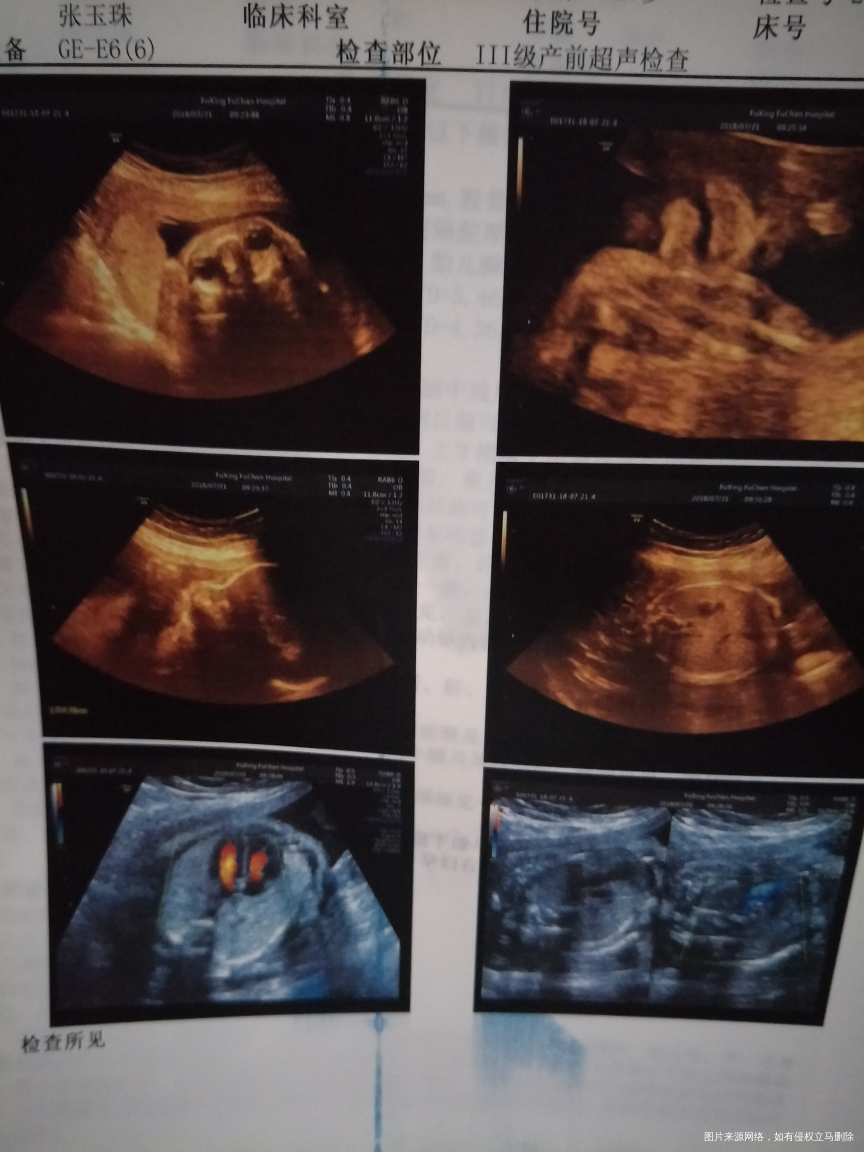

怀孕26+6,做的四维彩超,看不见宝宝的手指头和脚指头,正常吗?好担心啊,麻烦医生帮忙看看,

你好,宝妈。宝宝总体发育均正常,至于手指脚趾不清楚,多半宝宝体位有关。之后可以再次复查,定期产检,祝你好孕。如果我的建议对您有帮助,请记得选择点击采纳哦。

之前检查的nt和无创dna结果如何?

您好,检查报告正常的,定期产检,祝好孕!

补充说明:宝妈可以了解彩超最下面几行的说明,手脚,耳等等不是彩超检查的项目,因为毕竟宝宝在子宫内,除非MRI或是更高超的检查才能看见“细枝末节”。目前已经接近孕晚期,注意宝宝胎动,定期产检,祝你好孕。如果我的建议对您有帮助,请记得选择点击采纳哦。